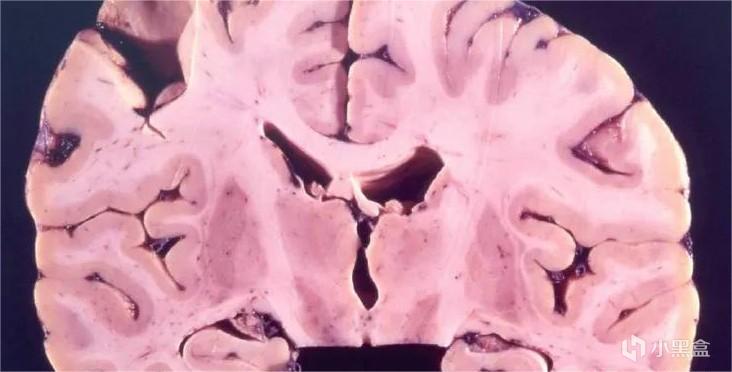

起初,盖杜谢克就察觉出了问题,这片脑子和他所熟悉的大脑并不一样,仿若一块满是空洞的海绵。

不过在进行了细致的检测之后,却又没在其中发现明显的问题。后来盖杜谢克将脑片中的微生物彻底清除掉,接着将脑组织注射进黑猩猩的大脑中,数月之后,黑猩猩果然发病,症状恰是典型的库鲁病。脑组织中的微生物都已被去除,致病因素究竟是什么呢?在进行了大量研究之后,谜底终于揭开了,致使库鲁病发生的缘由就是后来赫赫有名的朊病毒。